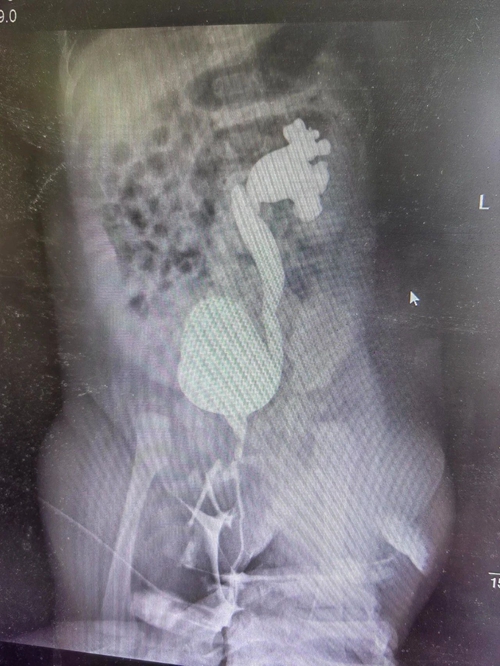

首先要找到患兒泌尿道感染及反復(fù)發(fā)熱的原因,才能對癥治療,根本性解決問題。腎臟免疫科團(tuán)隊進(jìn)一步完善各項檢查,發(fā)現(xiàn)患兒尿液細(xì)菌培養(yǎng)有大腸埃希菌,左腎腎積水,左側(cè)膀胱輸尿管返流(V級)……